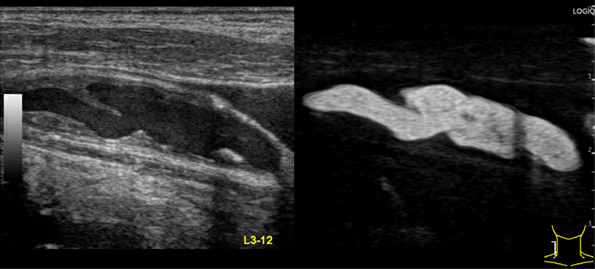

B-Flow*

微細な血流信号を増幅する独自のコード技術により血流を可視化。ドプラを使わずにBモードでの血流表示が可能に。Bモードとの重ね合わせ表示と2画面同時表示を搭載。